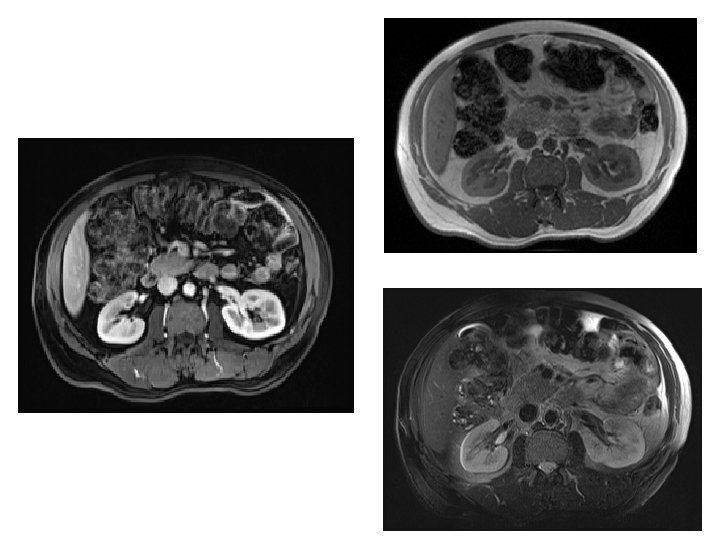

MRI • Better evaluation of soft tissue. • Expensive. • Useful for soft tissue pathology: tumor, infection.

MRI Image features: • Cross sectional images. • Image contrast determine by tissue properties. • Excellent for soft tissue evaluation.